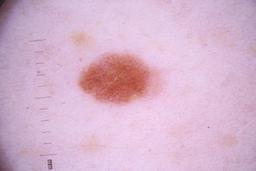

ISIC_4077341

Public

Information

- Created

- Dimensions

- 5184 x 3456

- Attribute to

- The University of Queensland Diamantina Institute, The University of Queensland, Dermatology Research Centre

- License

- CC-BY

- Used in

- Challenge 2020: Training

- Belongs to

- IP_1969685 IL_9238622

Clinical

| Field | Value |

|---|---|

| acquisition_day | 1 |

| age_approx | 50 |

| anatom_site_1 | Trunk |

| anatom_site_2 | Anterior trunk |

| concomitant_biopsy | False |

| dermoscopic_type | contact non-polarized |

| diagnosis_1 | Benign |

| diagnosis_confirm_type | serial imaging showing no change |

| family_hx_mm | False |

| image_type | dermoscopic |

| lesion_id | IL_9238622 |

| patient_id | IP_1969685 |

| personal_hx_mm | True |

| sex | male |

Columns

Showing first 50 images.